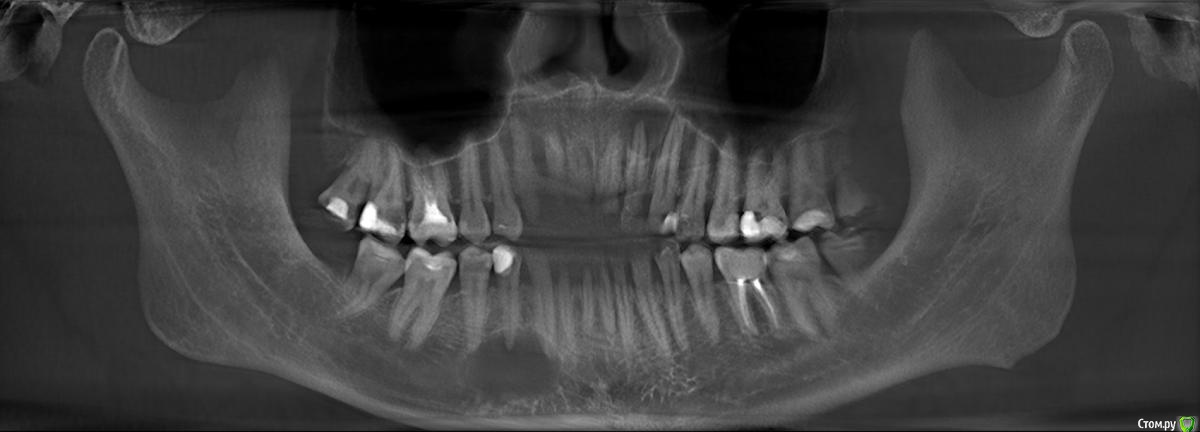

sewif Опубликовано 23 мая, 2021 Автор Поделиться Опубликовано 23 мая, 2021 Здравствуйте Сегодня сделал снимок. Прошу почти год с предыдущего снимка. В этот раз делал снимок как сказал доктор - в Пикассо. Программа непонятная и может скриншоты не очень, если нужно как-то иначе то прошу сообщить. Я не вижу кисты, ее нет или я не так смотрел? Ссылка на комментарий

Irouil Опубликовано 23 мая, 2021 Поделиться Опубликовано 23 мая, 2021 Эти картинки не особо показательны, конечно, но очевидно, что от изначальной ситуации тут не осталось примерно ничего 1 Ссылка на комментарий